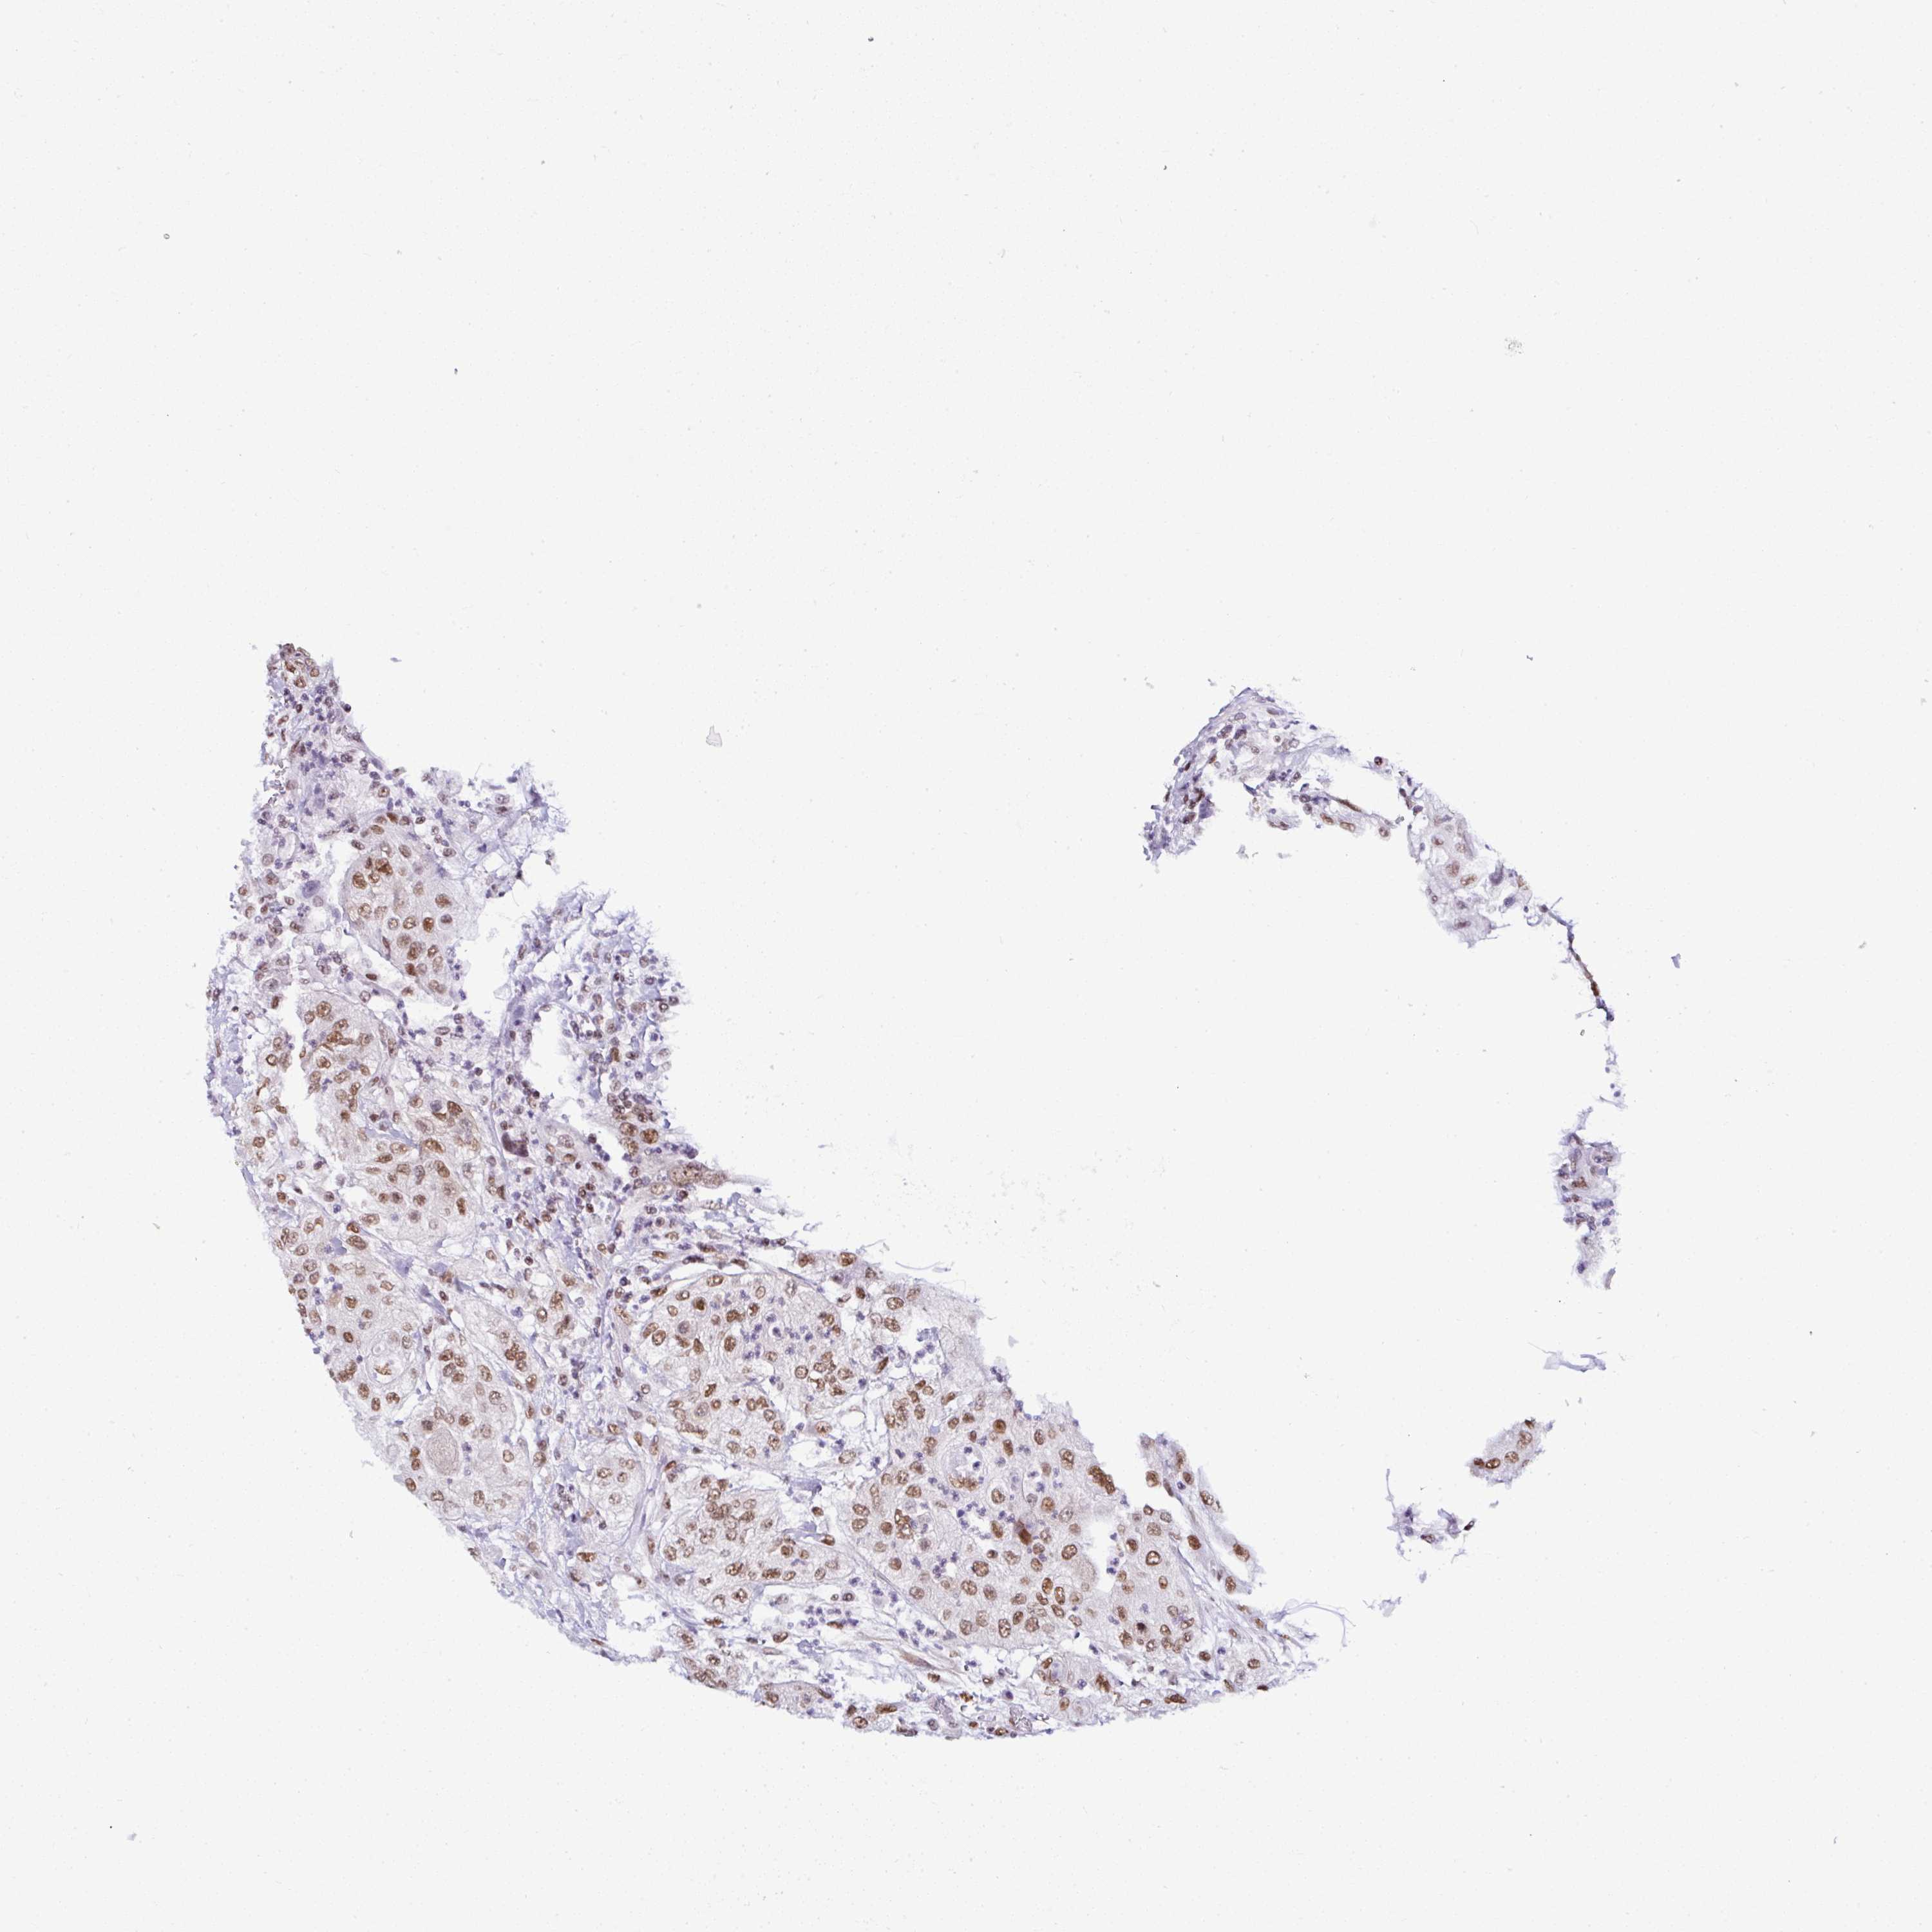

UROTHELIAL CANCER - Protein expressioni

A mouse-over function shows sample information and annotation data. Click on an image to view it in a full screen mode. Samples can be filtered based on level of antibody staining by selecting one or several of the following categories: high, medium, low and not detected. The assay and annotation is described here.

Antibody stainingi

Antibody staining in the annotated cell types in the current human tissue is reported as not detected, low, medium, or high, based on conventional immunohistochemistry profiling in selected tissues. This score is based on the combination of the staining intensity and fraction of stained cells.

Each image is clickable and will lead to virtual microscopy that enables deeper exploration of all samples and also displays staining intensity scores, fraction scores and subcellular localization as well as patient and tissue information for each sample.

Antibody HPA050785

Antibody HPA055308

Staining

High

Medium

Low

Not detected

Intensity

Strong

Moderate

Weak

Negative

Quantity

>75%

75%-25%

<25%

None

Location

Nuclear

Cytoplasmic/membranous

Cytoplasmic/membranous,nuclear

Urothelial carcinoma, High grade

Urothelial carcinoma, Low grade

Urothelial carcinoma, NOS